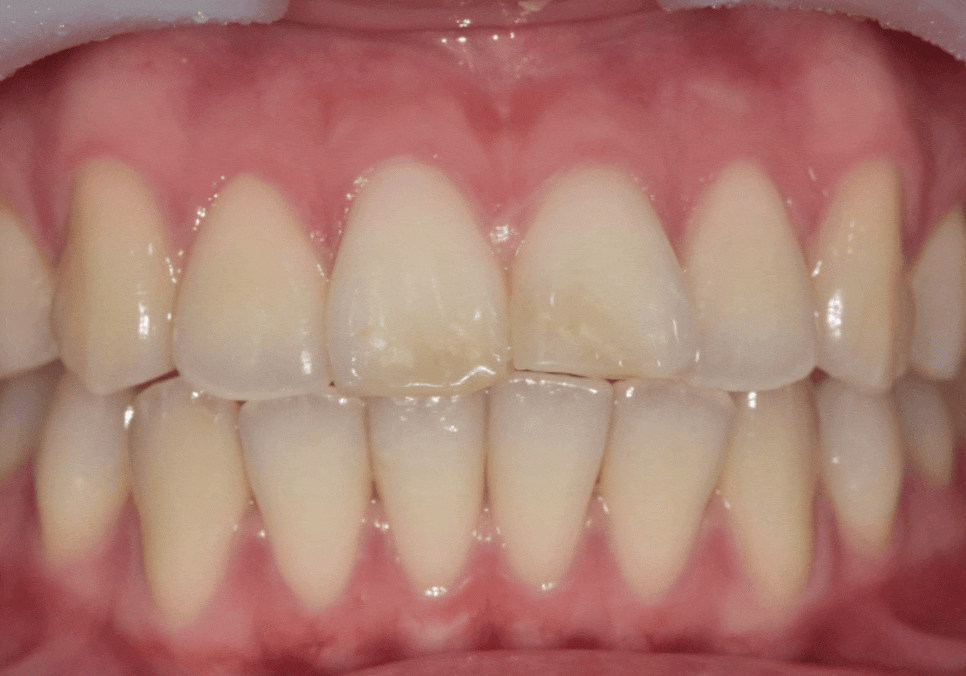

250203(전) 250410(후)

최종 라미네이트를 부착한 모습입니다.

· 양쪽 앞니 길이가 가지런해지고

· 앞으로 뻗어 보이던 느낌도 자연스럽게 완화되고

· 절단교합에서도 힘을 덜 받도록 안정적인 공간이 확보되었습니다.

제가 계획했던 대로 라미네이트가 제작되어

저 또한 뿌듯했던 것 같습니다.